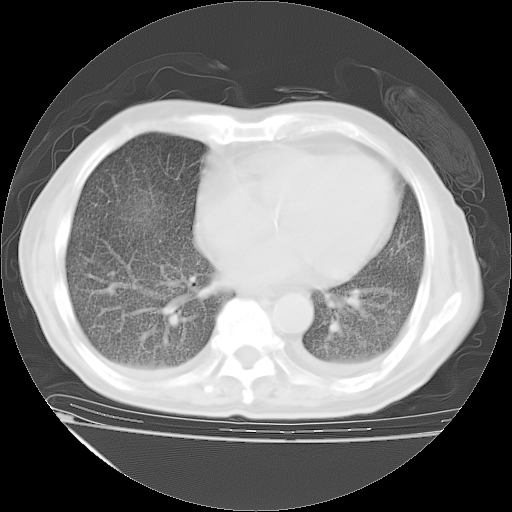

甲强龙80mg/日+抗结核治疗(异烟肼+利福霉素+乙胺丁醇)10天。复查肺部CT。

治疗10天肺部CT